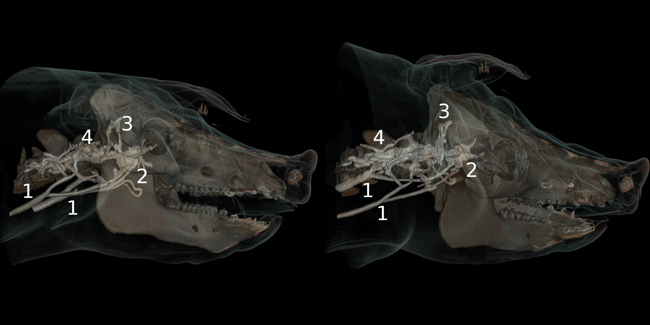

Gabriel Putzer, Judith Martini, Julian Wagner, Lisa Schnegg, Peter Mair

Poor outcome after cardiac arrest is caused mainly by irreversible brain damage during cardiopulmonary resuscitation (CPR). The brain’s tolerance of hypoxia is extremely low and situations of low flow or no flow, such as during CPR, can lead to rapid progression of oxygen deficit, resulting in brain metabolic shutdown and cell death. The main research focus of this group is on investigating mechanisms that are capable of increasing oxygen availability to the brain during CPR. In particular, the effect of vasopressors on cerebral perfusion pressure and oxygen delivery to the brain have been discussed controversially in the literature. Adrenalin, which has been used during CPR for decades, has been accused of diminishing microvascular perfusion, owing to strong vasoconstriction, which leads to poor oxygenation of downstream tissues. Recent results of this research group challenge this hypothesis by using a complex neuromonitoring model in pigs, which includes not only oxygenation parameters but also direct microvascular perfusion measurements and metabolic profiles.

Cardiopulmonary Resuscitation

- Putzer, G.; Martini. J.; Spraider, P.; Hornung, R.; Pinggera, D.; Abram, J.; Altaner, N.; Hell, T.; Glodny, B.; Helbok, R.; Mair, P.: Effects of different adrenaline doses on cerebral oxygenation and cerebral metabolism during cardiopulmonary resuscitation in pigs. RESUSCITATION. 2020; 156: 223-229

- Schiefecker, A.J.; Putzer, G.; Braun, P.; Martini, J.; Strapazzon, G.; Antunes, A.P.; Mulino, M.; Pinggera, D.; Glodny, B.; Brugger, H.; Paal. P.; Mair, P.; Pfausler, B.; Beer, R.; Humpel, C.; Helbok, R.: Total Tau-Protein as Investigated by Cerebral Microdialysis Increases in Hypothermic Cardiac Arrest: A Pig Study. THERAPEUTIC HYPOTHERMIA AND TEMPERATURE MANAGEMENT. 2020; online ahead of print

- Gaasch, M.; Putzer, G.; Schiefecker, A.J.; Martini, J.; Strapazzon, G.; Ianosi, B.; Thome, C.; Paal, P.; Brugger, H.; Mair, P.; Helbok, R.: Cerebral Autoregulation Is Impaired During Deep Hypothermia-A Porcine Multimodal Neuromonitoring Study. THERAPEUTIC HYPOTHERMIA AND TEMPERATURE MANAGEMENT. 2020; 10(2): 122-127

- Large animal experimental facility